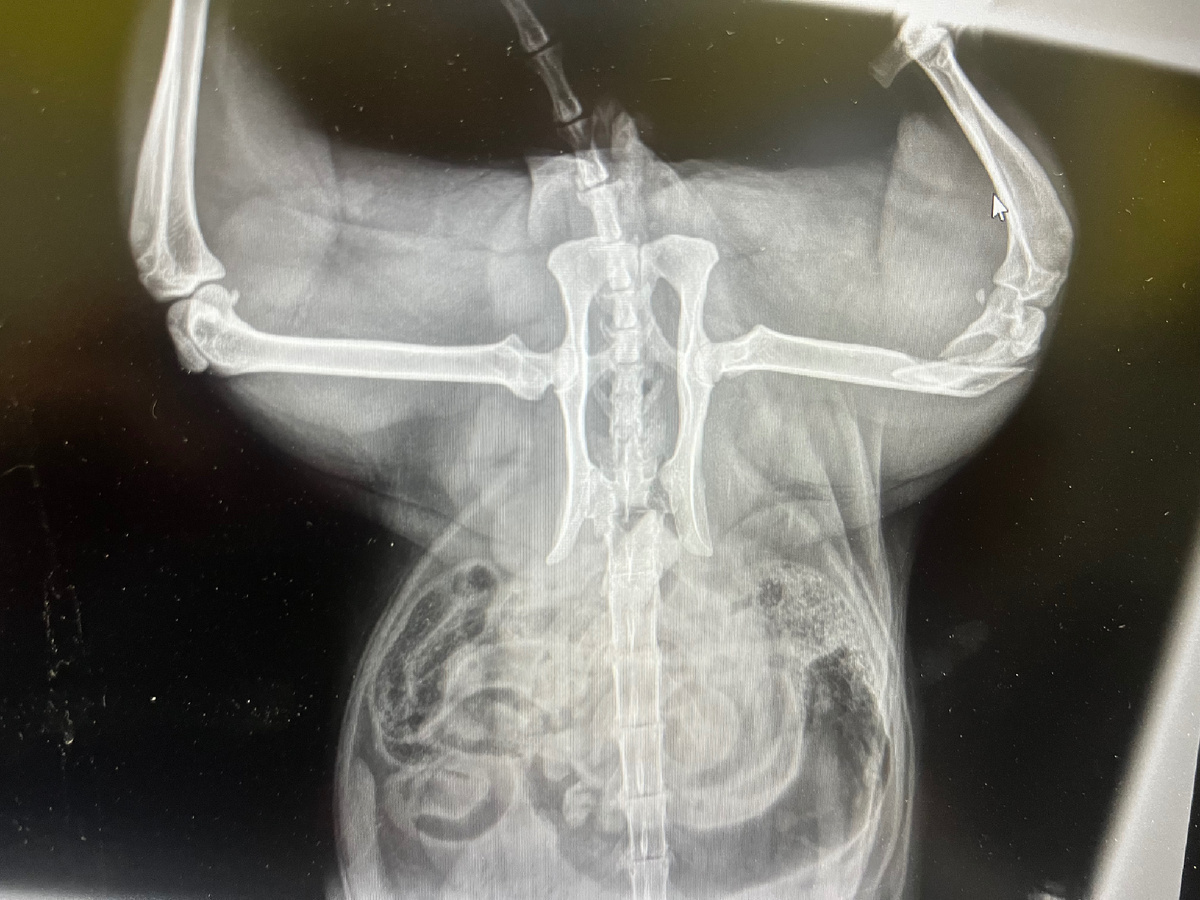

Сегодня был найден  во дворе многоквартирного дома, лежал, кричал и бился в конвульсиях😭 Мы отвезли сразу же котика на рентген и потом в ВетЛайф!

По рентгену у котика диафрагмальная грыжа, ЖЕЛУДОК ЗАШЕЛ В ГРУДНУЮ ПОЛОСТЬ И ПЕРЕЖАЛ ЛЕГКИЕ И СЕРДЦЕ, перелом коленного сустава и скорее всего сломан таз, отбит мочевой пузырь!!!! Так же на рентгене в котике обнаружили ПУЛЮ😡